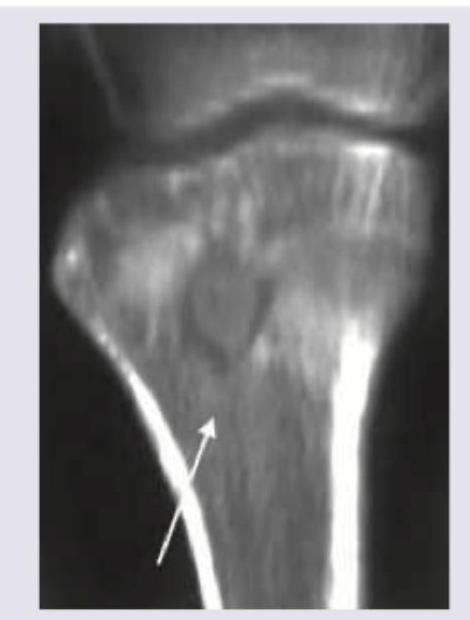

Which complication of osteomyelitis is shown below?

Explanation: ***Brodie's abscess*** - The image suggests a well-circumscribed, **radiolucent lesion** with a sclerotic rim within the bone, which is characteristic of a Brodie's abscess. - This is a subacute or chronic form of osteomyelitis, often appearing as a **focal lucency** in the metaphysis of long bones. *Garre's osteomyelitis* - This is characterized by **diffuse periosteal new bone formation** and cortical thickening, giving a "onion peel" appearance, which is not seen in the image. - It typically results from a low-grade infection and leads to **sclerosis and hypertrophy** of the bone. *Bony ankyloses* - **Bony ankylosis** refers to the fusion of two bones across a joint, resulting in immobility. - This image shows a lesion within a single bone, not a **fused joint**. *All of the above* - This option is incorrect because the image specifically depicts features of a Brodie's abscess, ruling out Garre's osteomyelitis and bony ankylosis. - Therefore, not all the conditions listed are represented in the provided image.